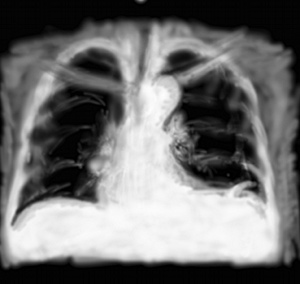

RP cancer bronchique

On sort de la pathologie aiguë avec la découverte d’une lésion mal limitée de petite taille, proche du hile, soit en aspect spiculé, soit en pseudo infiltrat alvéolaire mais trop court. Il peut s’associer une opacité arrondie toute proche du médiastin et correspondant à une adénopathie.

C’est un des modes de présentation du cancer du poumon. Malheureusement, ce n’est pas le seul, citons aussi un aspect difficile à détecter (voire impossible à diagnostiquer sur une radio d’urgence) du cancer bronchio-alvéolaire en toutes petites opacités type interstitielles mais localisées à moins qu’un segment pulmonaire. Les autres types sont une lésion pas visible mais sa conséquence avec l’atélectasie de tout un lobe, et la pleurésie métastatique. Dans bien des cas, la radiographie thoracique ne peut montrer un cancer débutant.